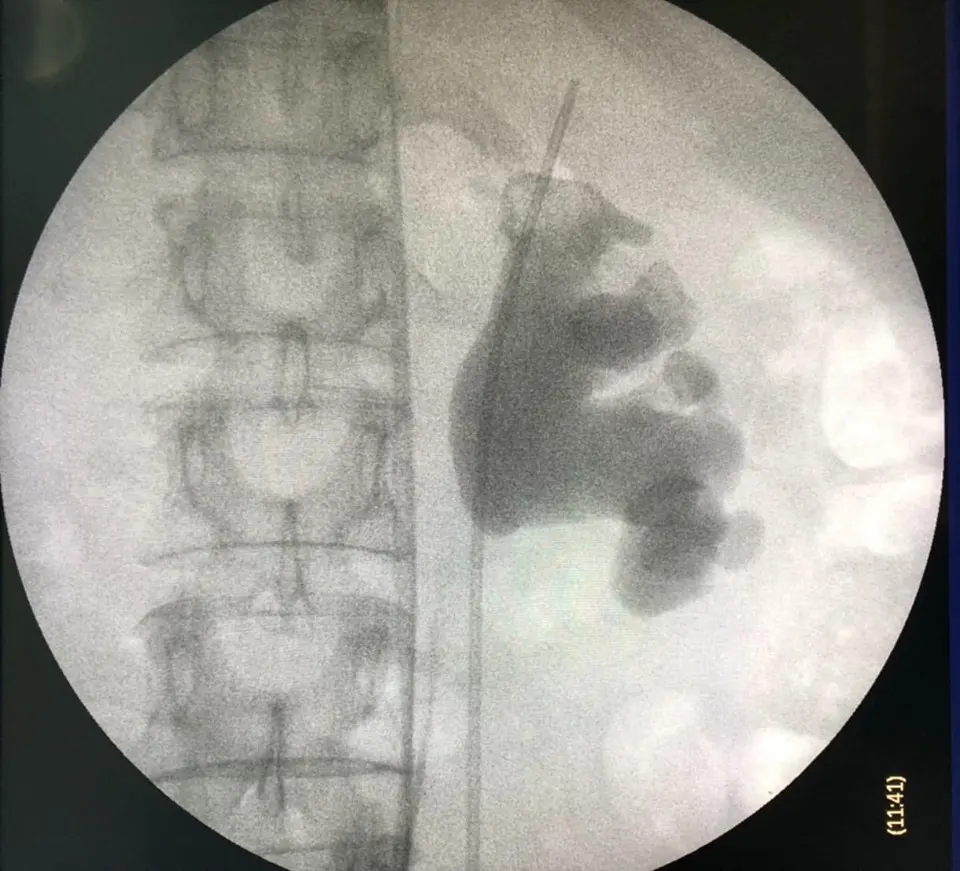

ตะลึง! กองนิ่วที่ผ่าตัดจากคนไข้รายเดียว!!

กองนิ่วที่ได้รับการผ่าตัดจากคนไข้รายเดียว หลังจากที่คนไข้รายนี้ต้องทนทุกข์ทรมานจากอาการปวดหลังและไตเสื่อม สุดตะลึง! เมื่อเข้ารับการผ่าตัดพบว่านิ่วเยอะมาก! จนสามารถนำมาเรียงให้เป็นคำว่านิ่วได้เลย

โดยภาพนี้ถูกโพสท์มาจากเฟซบุ๊กคุณ Sirianan Prasit คุณหมอที่โรงพยาบาลยะลา โดยได้โพสท์ข้อความระบุว่า ของกลางที่พบในคนไข้รายหนึ่ง หลังจากที่ต้องทนทุกข์ทรมานกับอาการปวดหลังและอาการไตเสื่อม

คงไม่ต้องบอกว่า......คืออะไร 😁😁😁 ไม่อยากเป็นนิ่ว โปรดดื่มน้ำวันละ6-8แก้วต่อวันครับ นิ่วในไตใหญ่เบ้อเริ่ม

Uro Yala Team